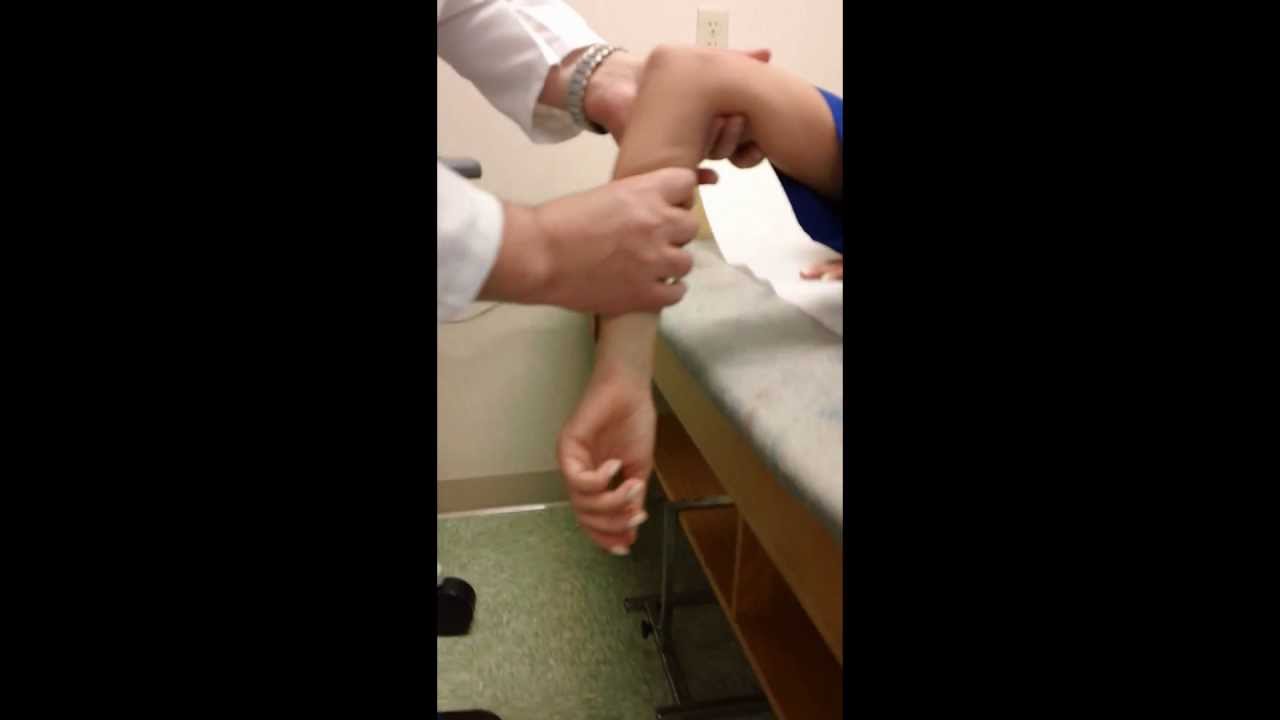

In this video we treat a patient with a posterior elbow dislocation. It is done gently and slowly. Ad browse & discover thousands of brands.

Sedation and muscle relaxers may be necessary to correct your elbow dislocation. This clip describes why elbow dislocation is hard to achieve in dogs, but when it occurs, how it is reduced. What are the risk factors for.